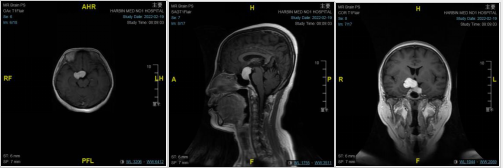

王宁了解病史完善相关检查诊断为巨大垂体腺瘤。由于患者肿瘤巨大,4厘米,上部向右侧生长,单纯经鼻内镜手术无法达到全切;下部有向海绵窦侵袭趋势,单纯开颅显微镜下手术亦无法达到直视下的安全完全切除。

王宁团队为患者完备术前检查,经过系统的评估考量后,决定采取个体化手术方案——国内领先的内镜-显微镜双镜联合技术为董女士肿瘤切除手术。在麻醉科和手术室配合下,王宁带领主治医生邵奇,住院医生房宇龙、孔繁一、王宏飞,顺利为患者切除肿瘤,术后患者视力下降明显缓解,并顺利出院。